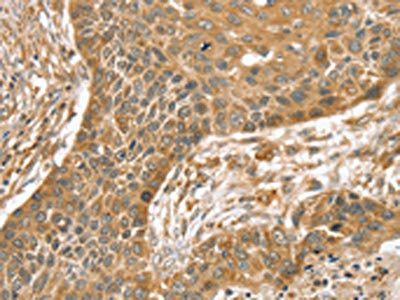

The image on the left is immunohistochemistry of paraffin-embedded Human liver cancer tissue using CSB-PA258249(SLIT1 Antibody) at dilution 1/35, on the right is treated with synthetic peptide. (Original magnification: ×200)

The image on the left is immunohistochemistry of paraffin-embedded Human esophagus cancer tissue using CSB-PA258249(SLIT1 Antibody) at dilution 1/35, on the right is treated with synthetic peptide. (Original magnification: ×200)